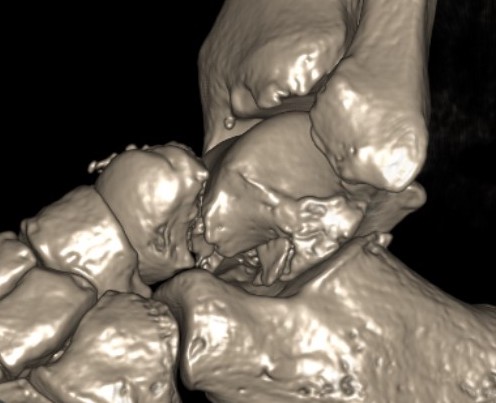

Canale view

- evaluates talar neck

- foot everted 15 deg

- look for medial shortening / varus